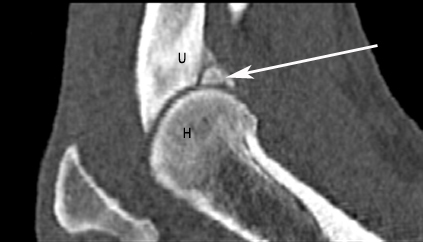

Nachdem ich bei „Oscar“ die Narkosefähigkeit geprüft hatte, haben wir einen Venenkatheter eingelegt und darüber die Narkose eingeleitet. „Oscar“ bekam einen Luftröhrentubus, damit in der Narkose die Atmung nicht behindert wird und er Narkosegase einatmen kann. „Oscar“ wurde für die Untersuchung der Ellbogengelenke in Brustlage mit gestreckten Vordergliedmaßen auf dem Untersuchungstisch gelagert und mit kontrastarmen Lagerungshilfen (z.B. Schaumstoffkeile oder Rohrisolationen) positioniert. Die reine Untersuchungszeit im CT beträgt für eine Ellbogensequenz ca. 10-15 Sekunden (120 kV, 200 mAs, Schichtdicke 0,75 mm, W 2500 L 500, Ellbogen beidseits transversal, nativ). Bei „Oscar“ fand ich auf diese Weise einen feinen Riss am inneren Kronfortsatz der Elle (Processus coronoideus medialis ulnae). Seine eigentliche Spitze war durch Entmineralisation bereits weniger röntgendicht. Als Folge dieses „Bruches“ war es zu einer Reizung des Gelenks und damit zu einer beginnenden Arthrose mit Ausbildung von Knochenspikes gekommen.